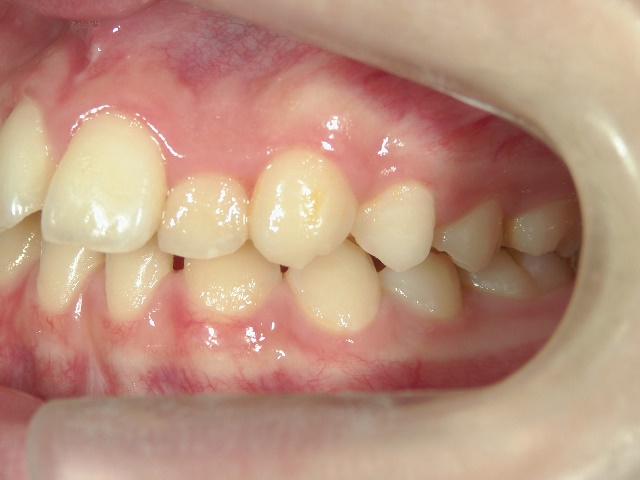

矯正歯科 治療前 左

矯正歯科 治療後 左